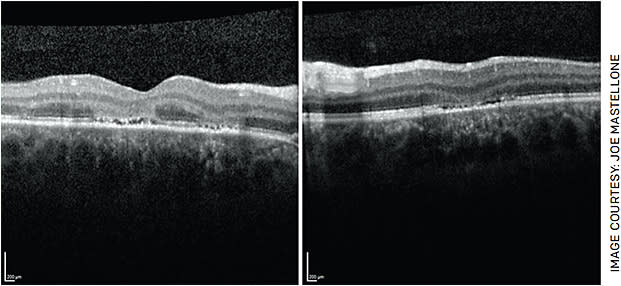

Our case presented with classic findings of APMPPE: a young patient with a preceding viral prodrome, rapid onset central scotoma OD and bilateral placoid lesions. Our patient was treated with 60 mg of prednisone for 3 days followed by 40 mg daily. Over the next 2 weeks, visual acuity improved from 20/100 to 20/30 in the right eye. Visual acuity remained 20/20 in the left eye despite the presence of lesions likely due to the sparing of the fovea. Repeat OCT macula demonstrated reconstitution of the ellipsoid zone and improving hyperreflectivity of the outer nuclear layer (Figure 4). Repeat FAF showed decreasing hyper-autofluorescence (Figures 5A and 5B). With time, the lesions are expected to become hypoautofluorescent due to RPE atrophy. Repeat fundus photos after 2 weeks showed decreased retinal whitening and increased subretinal pigmentation within the area of the lesions in both eyes (Figures 5C and 5D).